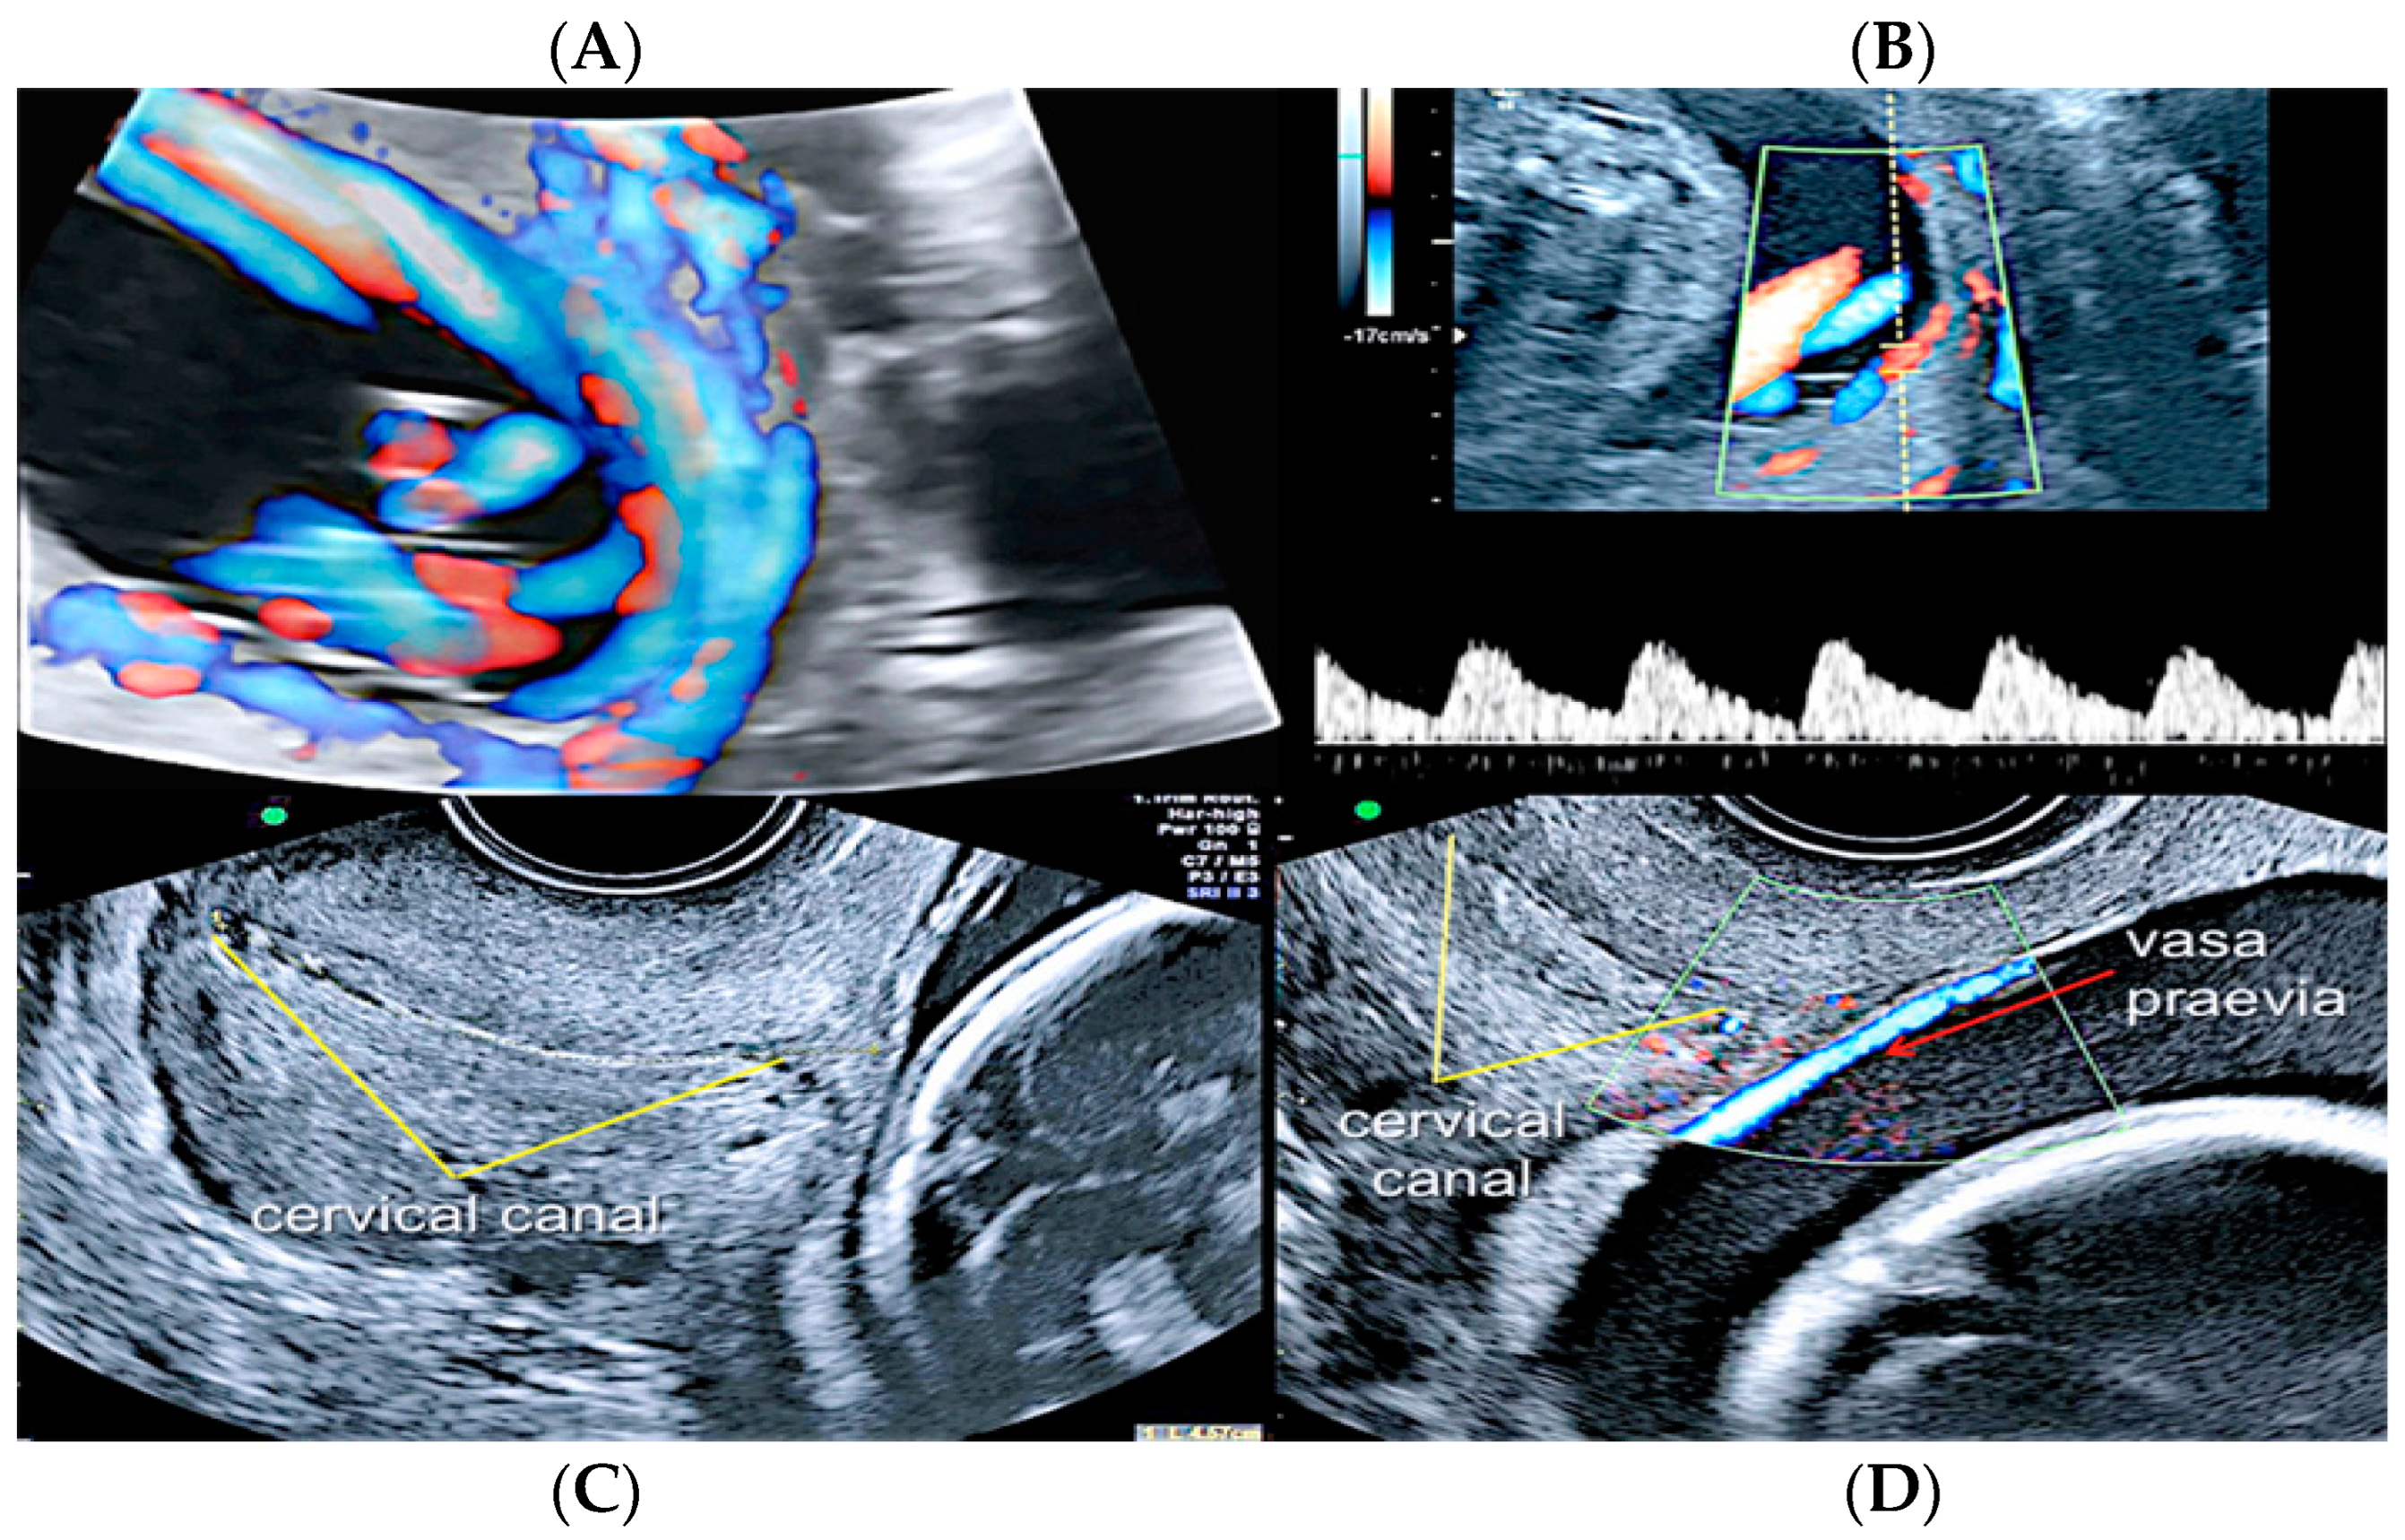

3.2.2. Vasa Praevia

Vasa praevia is a rare obstetrical pathology that affects 0.046% of all pregnancies, in which the fetal blood vessels are located within the membranes, not in their usual location protected by the umbilical cord or the placenta, and cover the internal cervical os [44,47]. Vasa praevia is classified into three types: Type I, when there is one single placental lobe with a velamentous cord; Type II, when the unprotected fetal vessels connect two lobes of a succenturiate lobed or bilobed placenta, near the cervix; and Type III, when the fetal vessel runs within the membranes, near the cervix, but is not associated with a velamentous cord insertion or bilobed placenta [48]. Vasa praevia has a resolution rate varying from 14% to 39% up to 28 weeks of gestational age, especially if diagnosed before 24 weeks of gestation, if not covering the internal cervical os and when not associated with placenta praevia [49]. These unprotected vessels are susceptible to rupture or compression, impairing fetal vascularization [40,46]. Perinatal survival rate is dependent on appropriate prenatal diagnosis and improves from 72% versus 97% when vasa praevia is detected antenatally [49,50]. Even if a correct prenatal diagnosis occurs, almost 70% of newborns receive NICU treatment due to the complications of prematurity [51,52,53,54]. Transvaginal ultrasound and color Doppler ultrasound are the gold standard diagnostic modalities [53]; however, due to the low incidence of this condition, there are no population screening protocols, and the screening approach is indicated only in high-risk patients [55,56], such as low-lying placenta/placenta praevia, velamentous cord insertion, ART and multiple gestations [52]. Elective Cesarean section should be planned around 35 weeks and not after 37 week’s gestation [57], and although no significant statistical differences were seen in the rate of neonatal complications between inpatient vs. outpatient management, in the outpatient group, a higher risk of an emergency Cesarean section was reported [58] (Figure 16 and Figure 17).

Figure 16.

Second trimester transvaginal scan and three-dimensional ultrasound with “glass-body” rendering (A), Doppler ultrasound (B) and two-dimensional ultrasound showing the anatomical relationship between the cervical canal (yellow lines) (C) and the presence of vasa praevia (red arrow) (D).

Figure 17.

Pregnancy at 24 weeks’ gestation. Two-dimensional ultrasound, color and pulse wave (PW) spectral Doppler ultrasound allowed the detection of an arterial vessel close to the internal cervical os (vasa praevia Type III, white arrows)(Legend: CC: cervical canal).